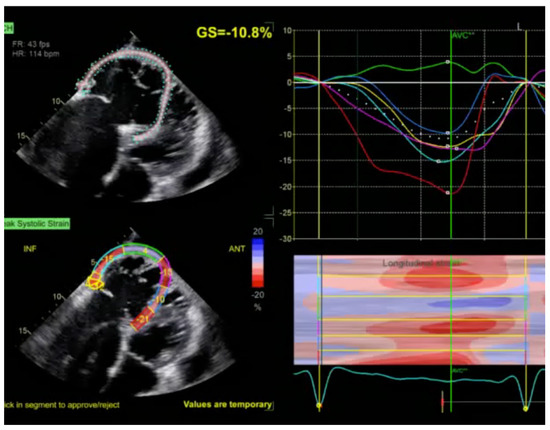

2.1. Echocardiography: The First Line of Diagnosis

- Gherbesi, E.; Gianstefani, S.; Angeli, F.; Ryabenko, K.; Bergamaschi, L.; Armillotta, M.; Guerra, E.; Tuttolomondo, D.; Gaibazzi, N.; Squeri, A.; et al. Myocardial strain of the left ventricle by speckle tracking echocardiography: From physics to clinical practice. Echocardiography 2024, 41, e15753. [Google Scholar] [CrossRef]